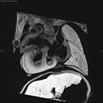

Caption Play Movie2D serial EFIC image stack in the coronal view of E15.5 mutant 1230-007-3 reveals situs inversus totalis

Copyright This image is from the Laboratory of Dr. Cecilia Lo, a member of the Cardiovascular Development Consortium (CvDC), Bench to Bassinet (B2B) program of the National Heart Lung and Blood Institute (NHLBI), and is displayed with the permission of the authors. J:175213

Pskh1b2b1230Clo protein serine kinase H1; Bench to Bassinet Program (B2B/CVDC), mutation 1230 Cecilia Lo

Pskh1b2b1230Clo/Pskh1b2b1230Clo C57BL/6J-Pskh1b2b1230Clo